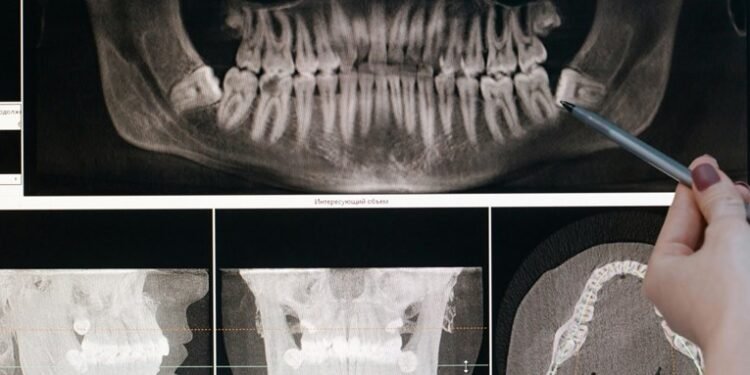

Tədqiqatın arxasında duran komanda ağız sağlamlığının əhəmiyyəti haqqında məlumatlılığı artırmaq istəyir. Mütəmadi olaraq diş həkiminə baş çəkmək, gündə iki dəfə dişlərinizi fırçalamaq və siqareti tərgitmək dişlərin sağlam olmasının açarıdır. Diş müayinələri yaşlı insanlarda xəstəlik və ölüm riskini izləmək üçün etibarlı üsul ola bilən dişlərin sayına və protezlər kimi həllərin tətbiqinə nəzarət etməyə imkan verir.